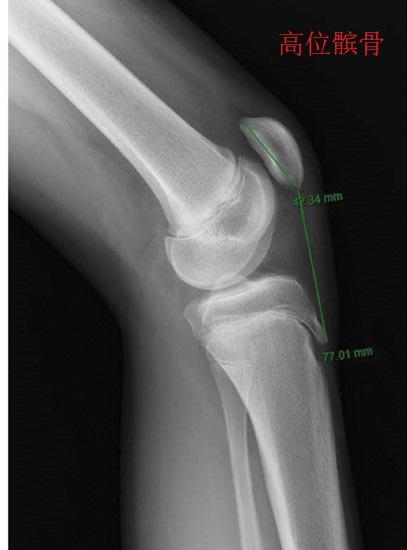

高位髌骨 高位髌骨是指髌骨在膝关节屈伸动作中的位置偏高,使其不能沿正常的轨迹滑动,并因为力线畸变而使髌骨出现额外的负载、磨损及多种应力反应。高位髌骨的主要症状就是膝关节活动受限、疼痛,可能与韧带松弛、胫骨结节病、髌骨支持带损伤等原因有关。